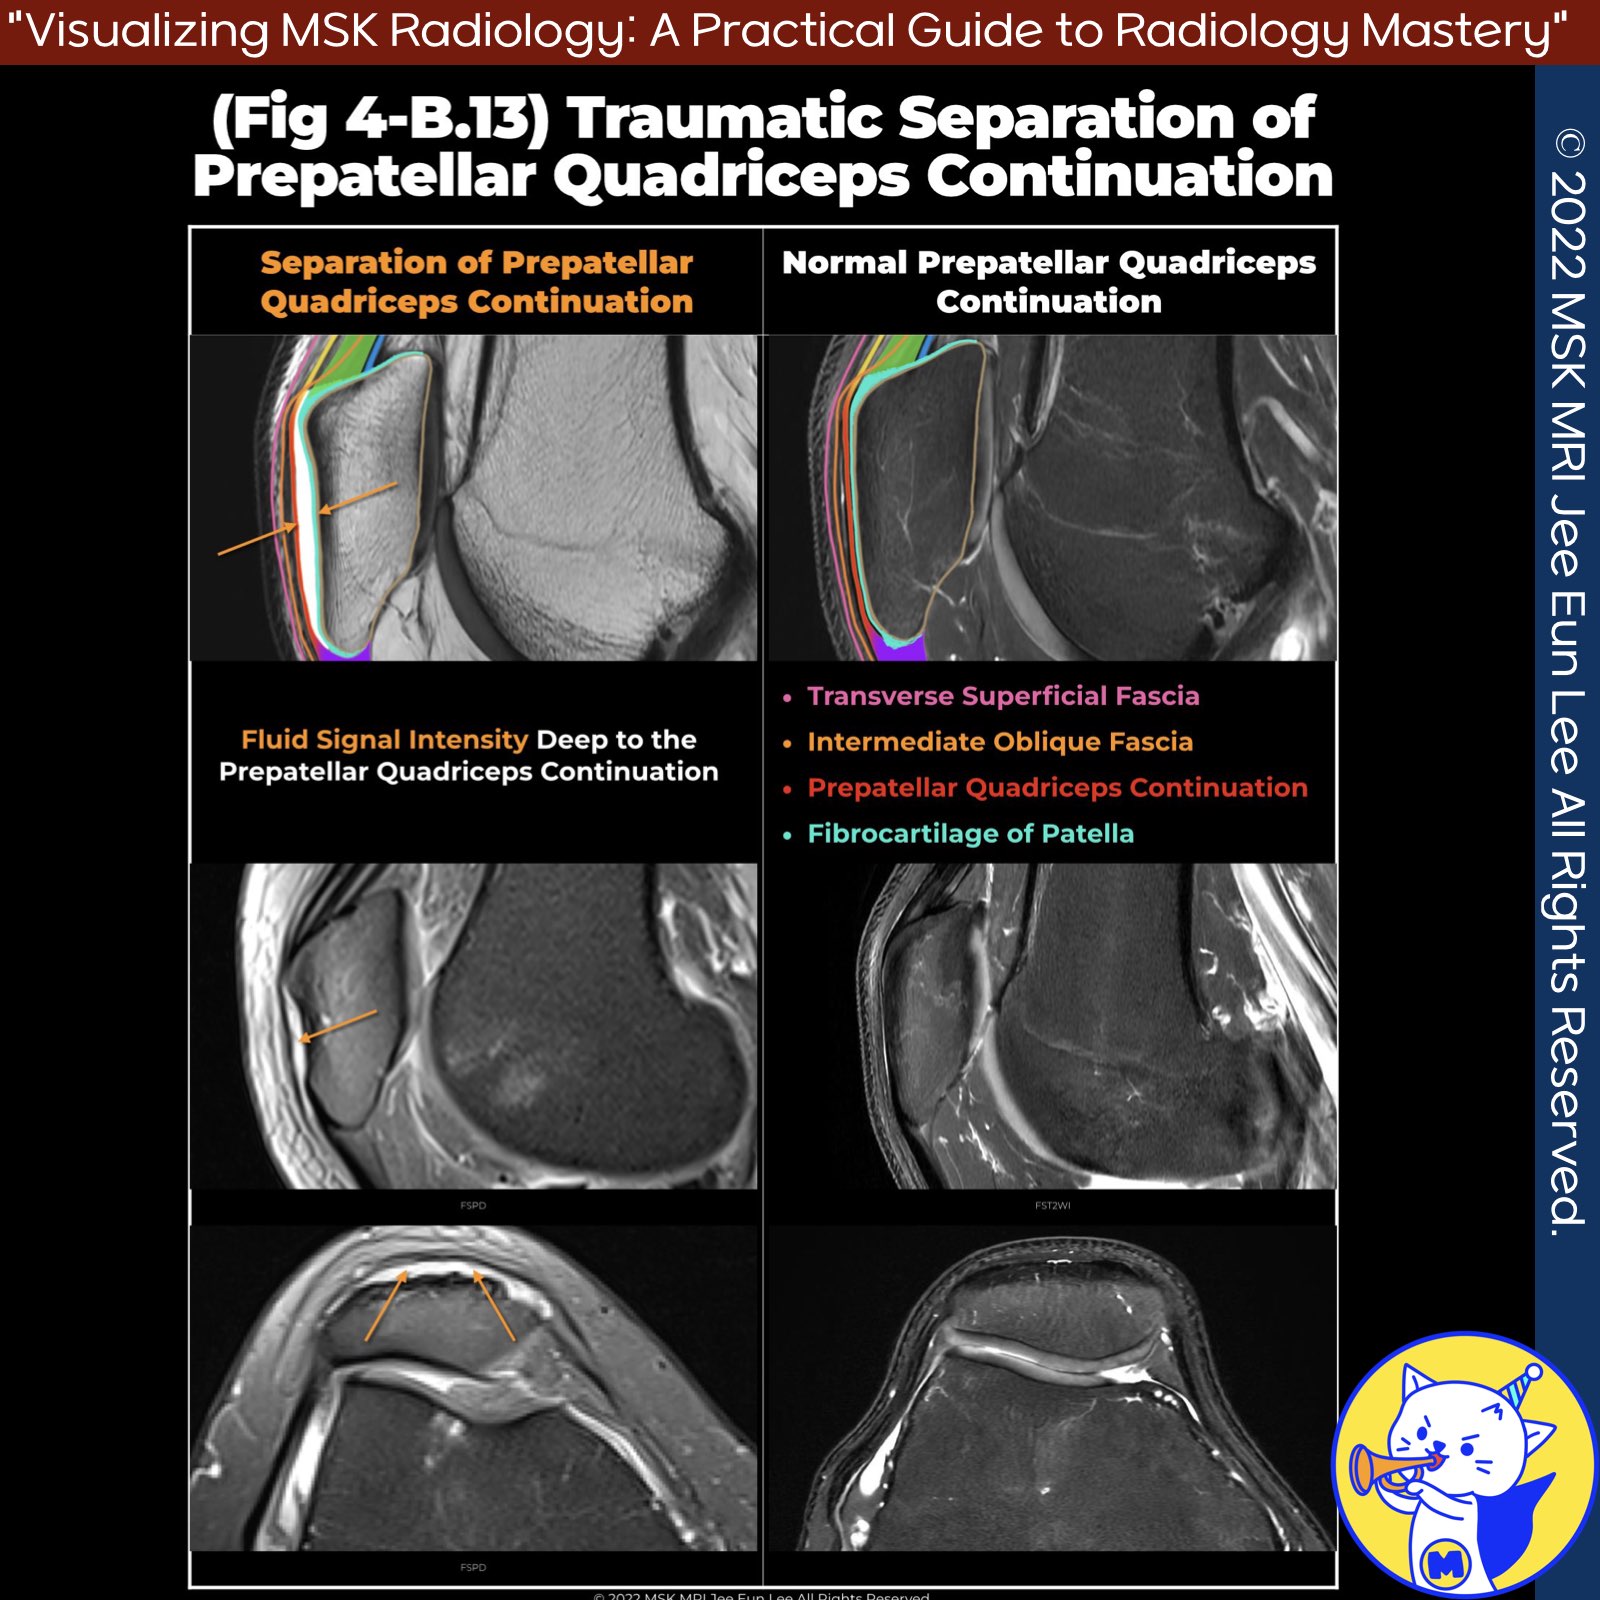

📌Anatomy Review Prepatellar Quadriceps Continuation

- Normally no space between prepatellar quadriceps continuation and anterior patella

- Small fibrocartilage layer can detach from bone, minimizing friction (AJR 2009)

- May explain traumatic separation of this layer from patella without tendon disruption

📌Separating Prepatellar Quadriceps Continuation

- Appears as thin fluid anterior to patella with intact tendons

- Seen in patients with anterior knee pain (AJR 2009)

- Do not mistake for simple prepatellar bursitis (MRI Web Clinic 2014)

✅ Key Teaching Points

- Prepatellar fluid could represent bursitis or deeper injury to prepatellar quadriceps continuation

- Attachment of this layer may be disrupted in trauma

- Has implications for injury type and treatment approach